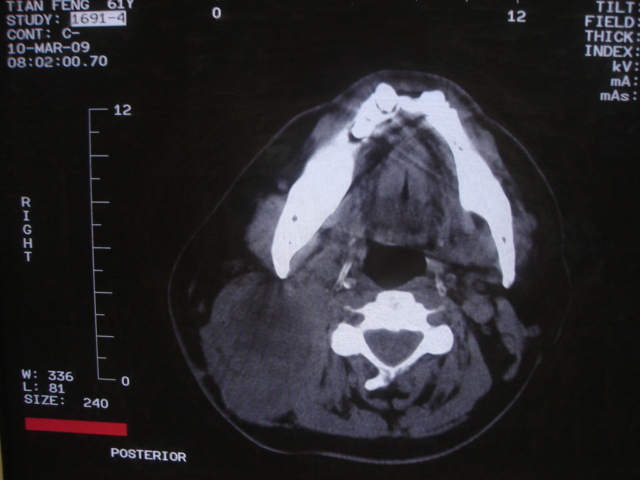

患者 男 61  甲状腺ca术后7年 颈部淋巴结转移

颈部多个淋巴结增大,结合甲状腺ca术后7年病史考虑转移。

右侧颈部淋巴结转移,右声带乳头突起,乳头状瘤可能性大。

1)右侧颈部淋巴结转移瘤。2)右侧声带新生物,性质待定;建议喉镜检查(活检)。